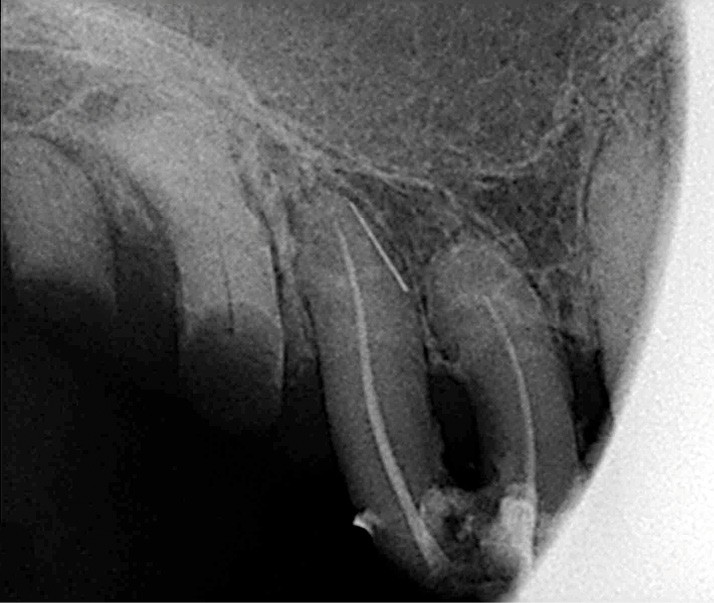

À la mandibule, nous notons que :

– les dents 45, 46, et 47 sont absentes ;

– la dent 37 est liée à 36 par un jonc retenu dans un composite et présente une image apicale et une alvéolyse distale dépassant le tiers de la racine. L’édentement n’a jamais été compensé.